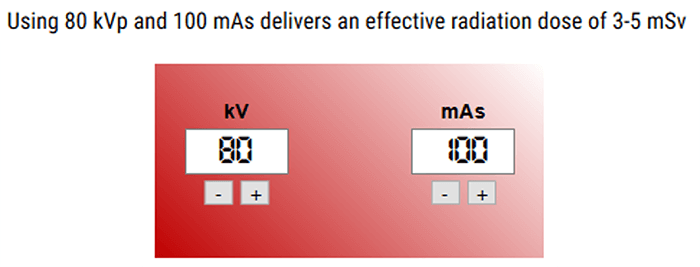

Knowing the fact that the use of CT perfusion imaging is increasing, the need for efficient radiation-reduction strategies is important. In most cases, brain perfusion CT images are acquired with tube currents ranging from 100-200 mAs. This level of radiation produces photons with a mean energy close to the K edge of Iodine, which optimizes the signal-to-noise ratio.

However, with the new technology, a number of strategies have been adopted successfully to lower mA and kV, among which are lower temporal sampling, iterative reconstructions, and increased pitch.